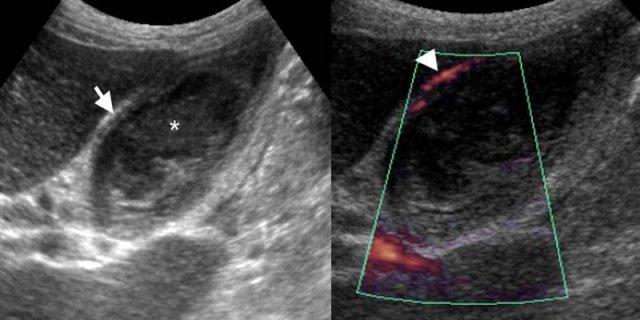

Bệnh nhân nam 74 tuổi với viêm túi mật cấp không có sỏi. TRÁI: Siêu âm tại vị trí đau tối đa cho thấy thành túi mật dày (mũi tên), lòng túi mật chứa đầy cặn lắng (dấu hoa thị) mà không có sỏi. PHẢI: Siêu âm Doppler năng lượng cho thấy tăng sinh mạch thành túi mật (đầu mũi tên), là dấu hiệu hỗ trợ chẩn đoán viêm.

Viêm túi mật không có sỏi

Viêm túi mật cấp không có sỏi chủ yếu xảy ra ở bệnh nhân nặng, được cho là do độ nhớt mật tăng cao từ việc nhịn ăn và các thuốc gây ứ mật.

Các đặc điểm hình ảnh tương tự như viêm túi mật cấp, ngoại trừ việc không có sỏi trong khi cặn lắng túi mật thường hiện diện (Hình).

Do ở bệnh nhân nặng, các bất thường túi mật thường gặp thứ phát do bệnh lý toàn thân (xem bên dưới), viêm túi mật không có sỏi có thể khó chẩn đoán [5].

Ở những bệnh nhân này, dẫn lưu túi mật qua da vừa có giá trị chẩn đoán vừa có tác dụng điều trị.